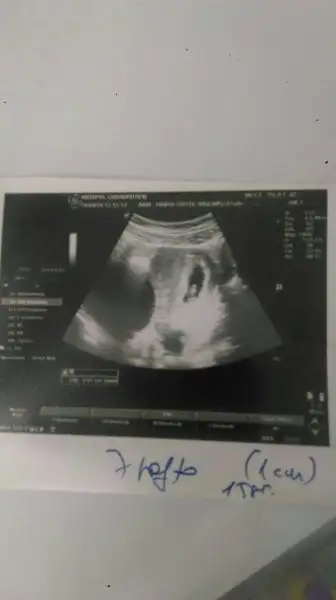

Hımm doktor bebek solda mi demişti öyleyse benim ki de sağda :) oy annesi yesin onu :)))öyle değildi benimki farklıydı :) ama eşim videomu cekmişti benim hastanede. kalp atışlarını duymak için. burdan videoyu size yollamak isteirm yollanabiliyorsa. benim sağımda kistim var, solumda bebek. monitorden bakınca kist solda gözüküyor yani tam tersi.

sana 7 ahftalıkken fotomu yolluyorum. bak kağıtta sağ yukarı tarafta. :) ama esasen solumda. kağıttaki soldaki de kocaman bir kist :)Hımm doktor bebek solda mi demişti öyleyse benim ki de sağda :) oy annesi yesin onu :)))

5 cmmiş bir zararı yokmuş. yavaş yavaş gecicek dedi. gecmezse alıcaz dedi doğumdaKist neden bu kadar büyük bi zararı yok mubenimki tembel yatıyo seninki dik duruyo :))